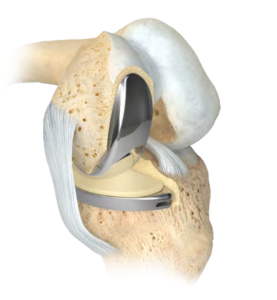

La prothèse unicompartimentale est un « resurfaçage », elle ne va pas modifier la géométrie du genou, mais va simplement se positionner à la place du cartilage retiré. Elle est composée de 3 pièces : un implant fémoral (sorte de patin), un implant tibial (embase) et un insert en polyéthylène (plastique hautement résistant) qui se loge entre les 2 composants métalliques.  L’avantage de la prothèse unicompartimentale par rapport à la prothèse totale est qu’il s’agit d’une chirurgie moins invasive, qui respecte l’enveloppe ligamentaire du genou et qui restitue une mécanique du genou que l’on peut qualifier de normale.

L’avantage de la prothèse unicompartimentale par rapport à la prothèse totale est qu’il s’agit d’une chirurgie moins invasive, qui respecte l’enveloppe ligamentaire du genou et qui restitue une mécanique du genou que l’on peut qualifier de normale.

Certaines conditions sont indispensables pour pouvoir proposer cette intervention : faible déformation du genou, absence de raideur importante, présence du ligament croisé antérieur, absence d’obésité, absence de maladie inflammatoire du genou… Si ces critères ne sont pas réunis, il faudra s’orienter vers la prothèse totale du genou. On estime qu’environ 10 % des prothèses de genou sont unicompartimentales. Une des indications préférentielles est l’ostéonécrose du condyle fémoral (interne le plus souvent).

L’incision cutanée mesure environ 10 cm. Le premier temps opératoire consiste à explorer le genou et confirmer l’indication de prothèse unicompartimentale. Puis, à l’aide d’instruments très précis (guides de coupes), le chirurgien va retirer la zone de cartilage malade et y implanter la prothèse.

a échoué, la seule solution chirurgicale est la prothèse totale du genou. Elle consiste à remplacer les 2 compartiments fémorotibiaux (interne et externe), avec ou sans remplacement de la rotule (resurfaçage).

La prothèse comporte donc une pièce fémorale, une pièce tibiale, toutes 2 métalliques, et un insert en plastique (polyéthylène) hautement résistant entre l’implant fémoral et tibial, et parfois un implant en polyéthylène sur la rotule.